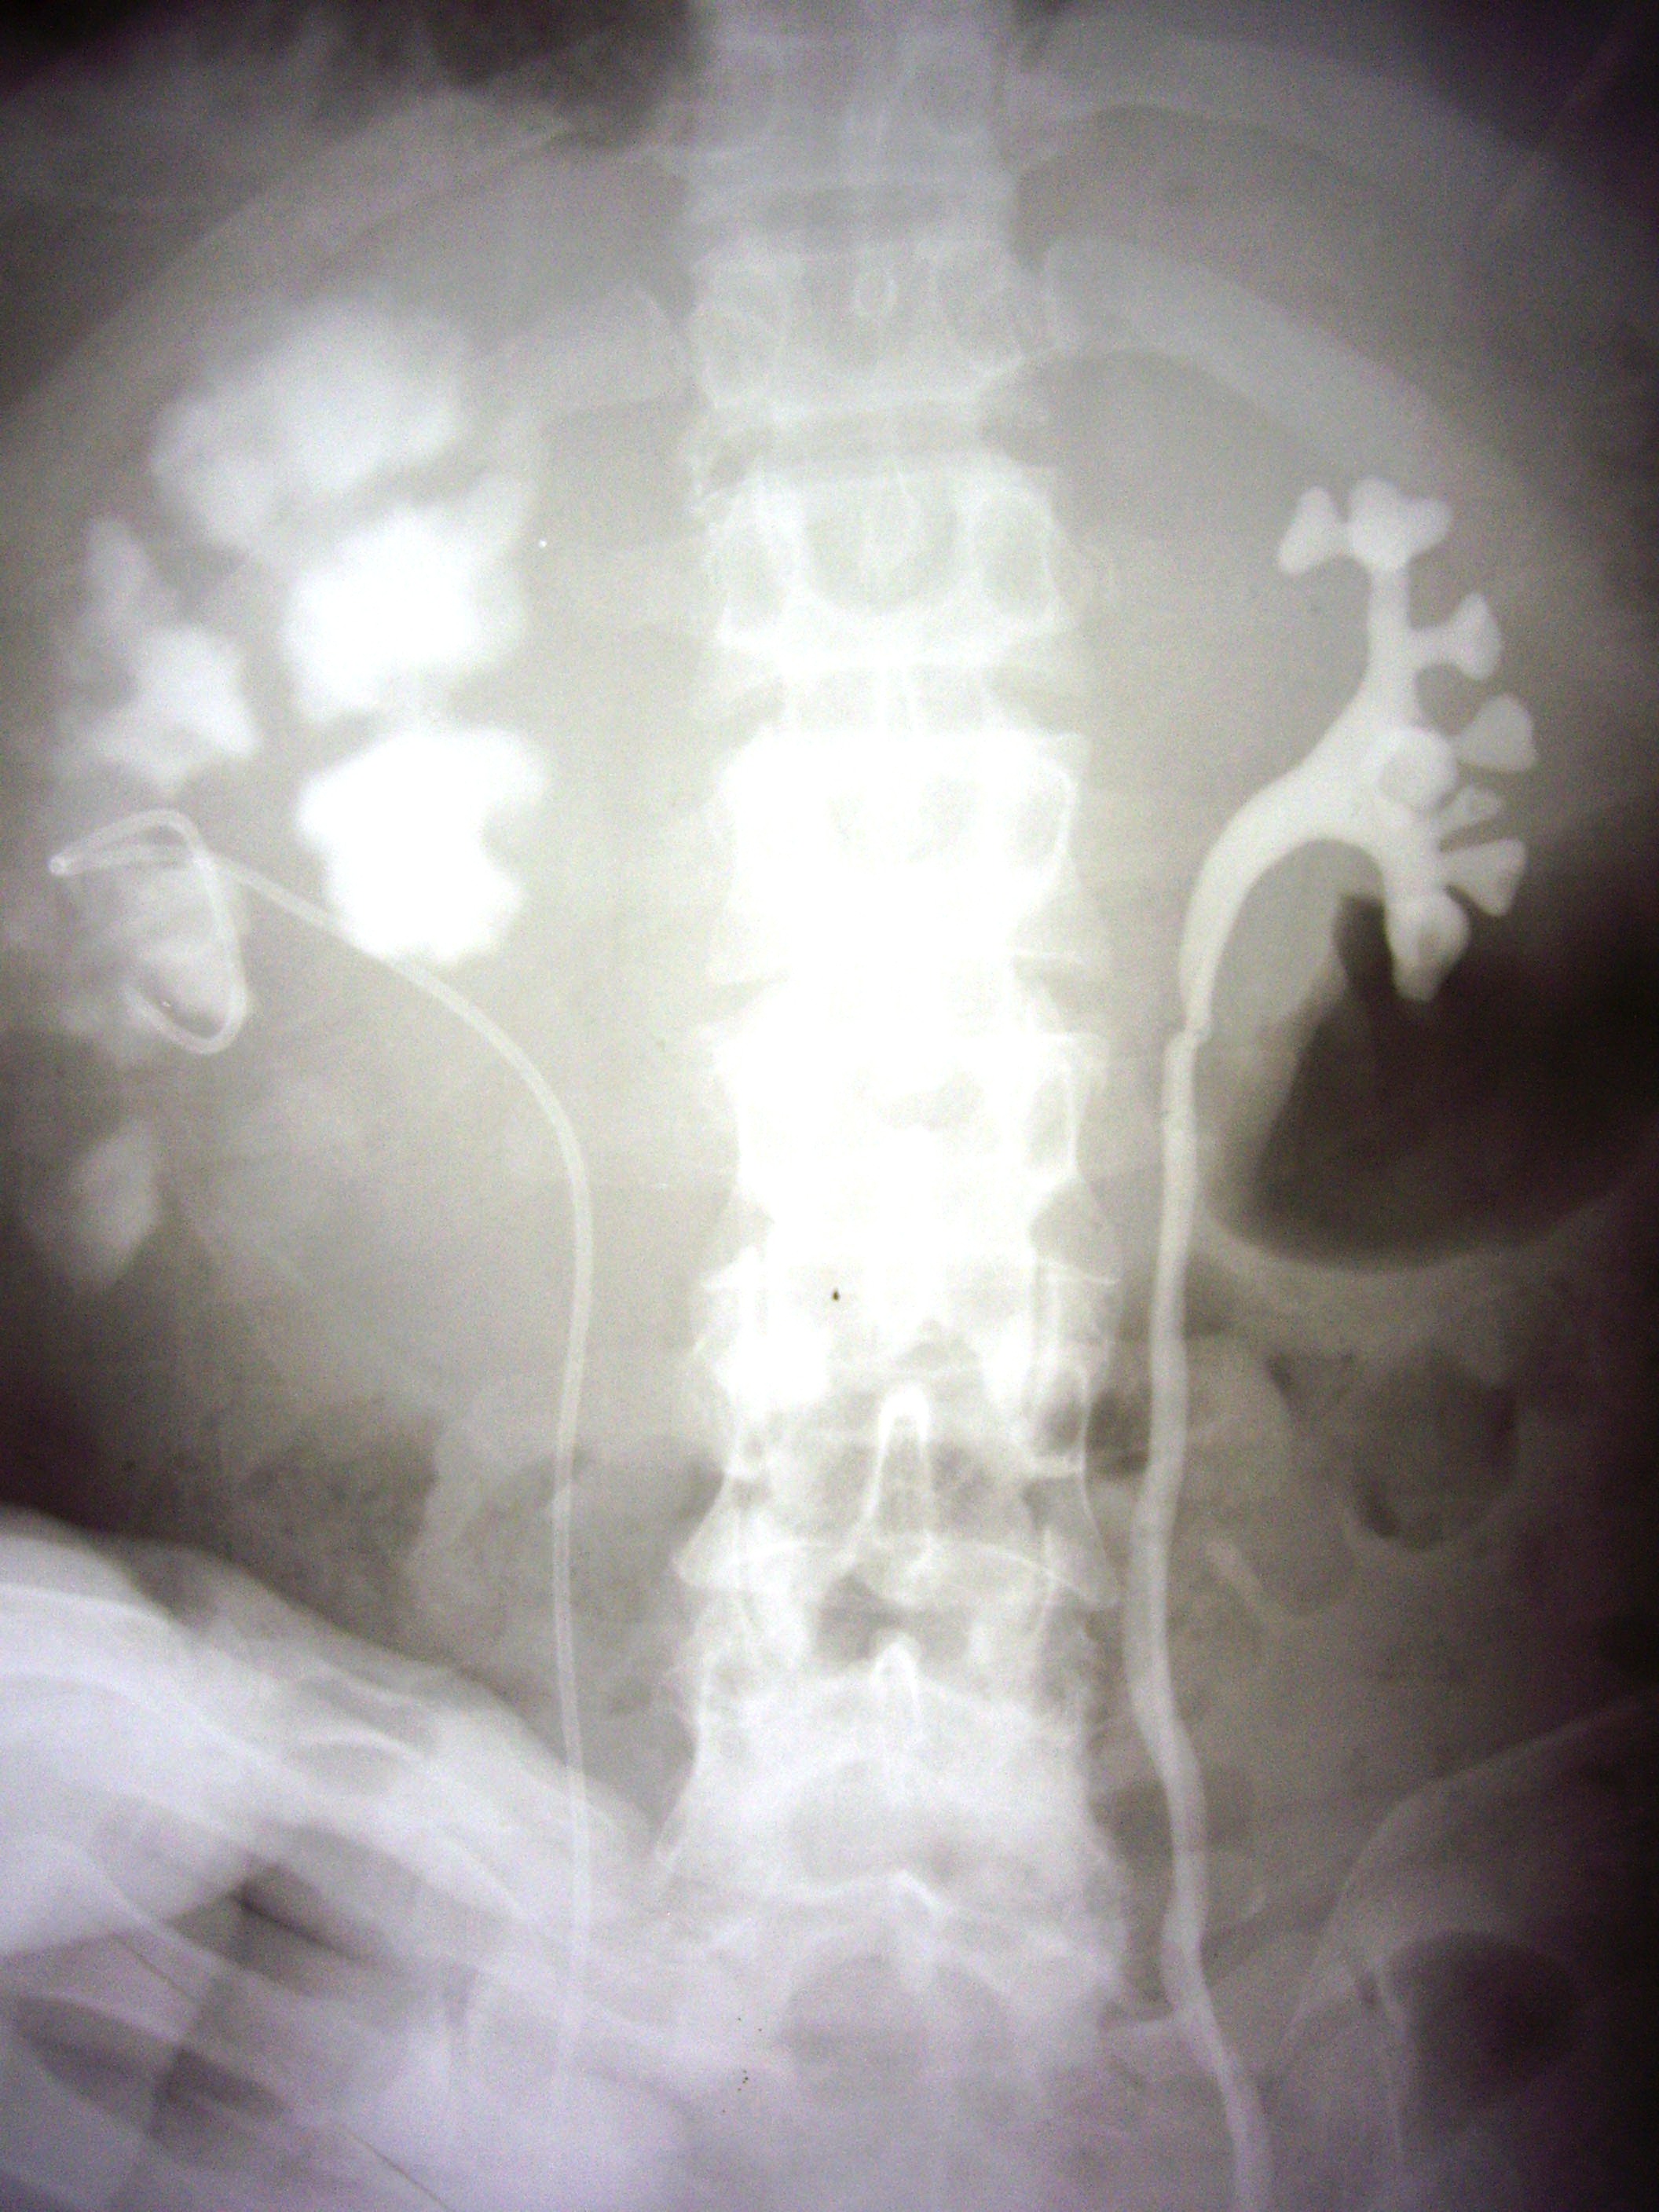

- Figure 5: Retrograde pyelogram showing multiple cavities in the right kidney caused by TB caseous necrosis

- Figure 6: IVP showing hydronephrosis due to ureteric TB